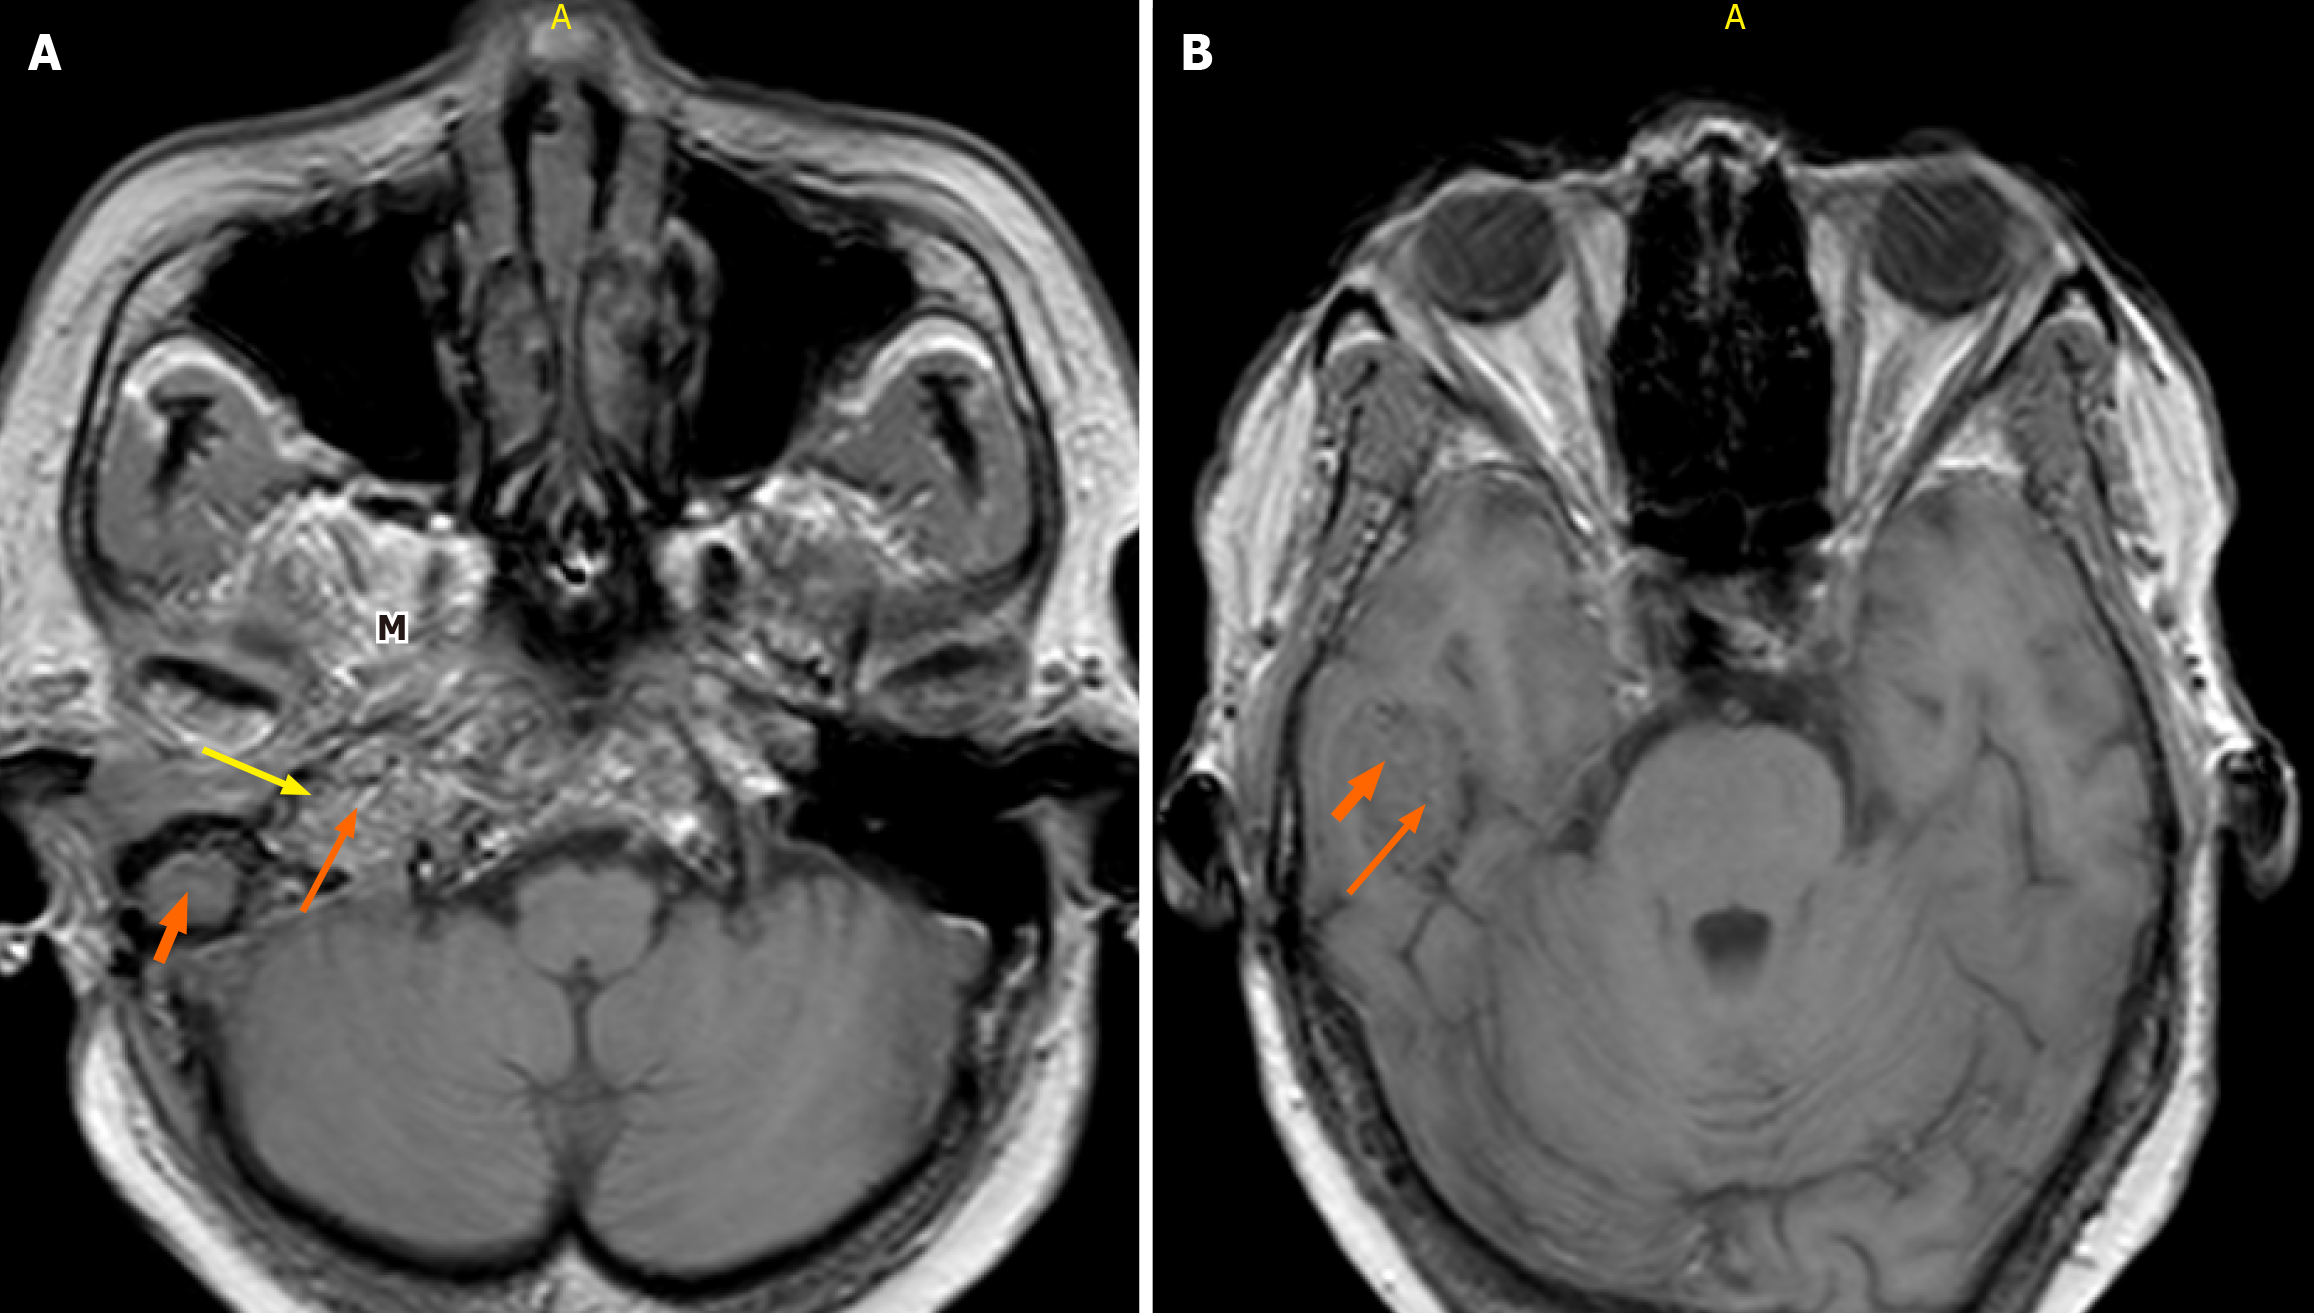

Figure 3 Axial non-contrast-enhanced T1-weighted magnetic resonance imaging of the brain (fast field echo sequence; repetition time 600 milliseconds, echo time 15 milliseconds, flip angle 25°, 3-mm slice thickness).

A and B: Of the brain demonstrates a poorly defined heterogeneous mass of slight hyperintensity and hypointensity centered at the right jugular fossa. A: Characteristic “salt” and “pepper” appearance is observed with punctate regions of hyperintensity representing the “salt” and small flow voids representing the “pepper” (long orange arrow and yellow arrow, respectively). Middle ear extension (thick short arrow) and masticator space (M) are seen; B: The right temporal lobe extension is demonstrated.